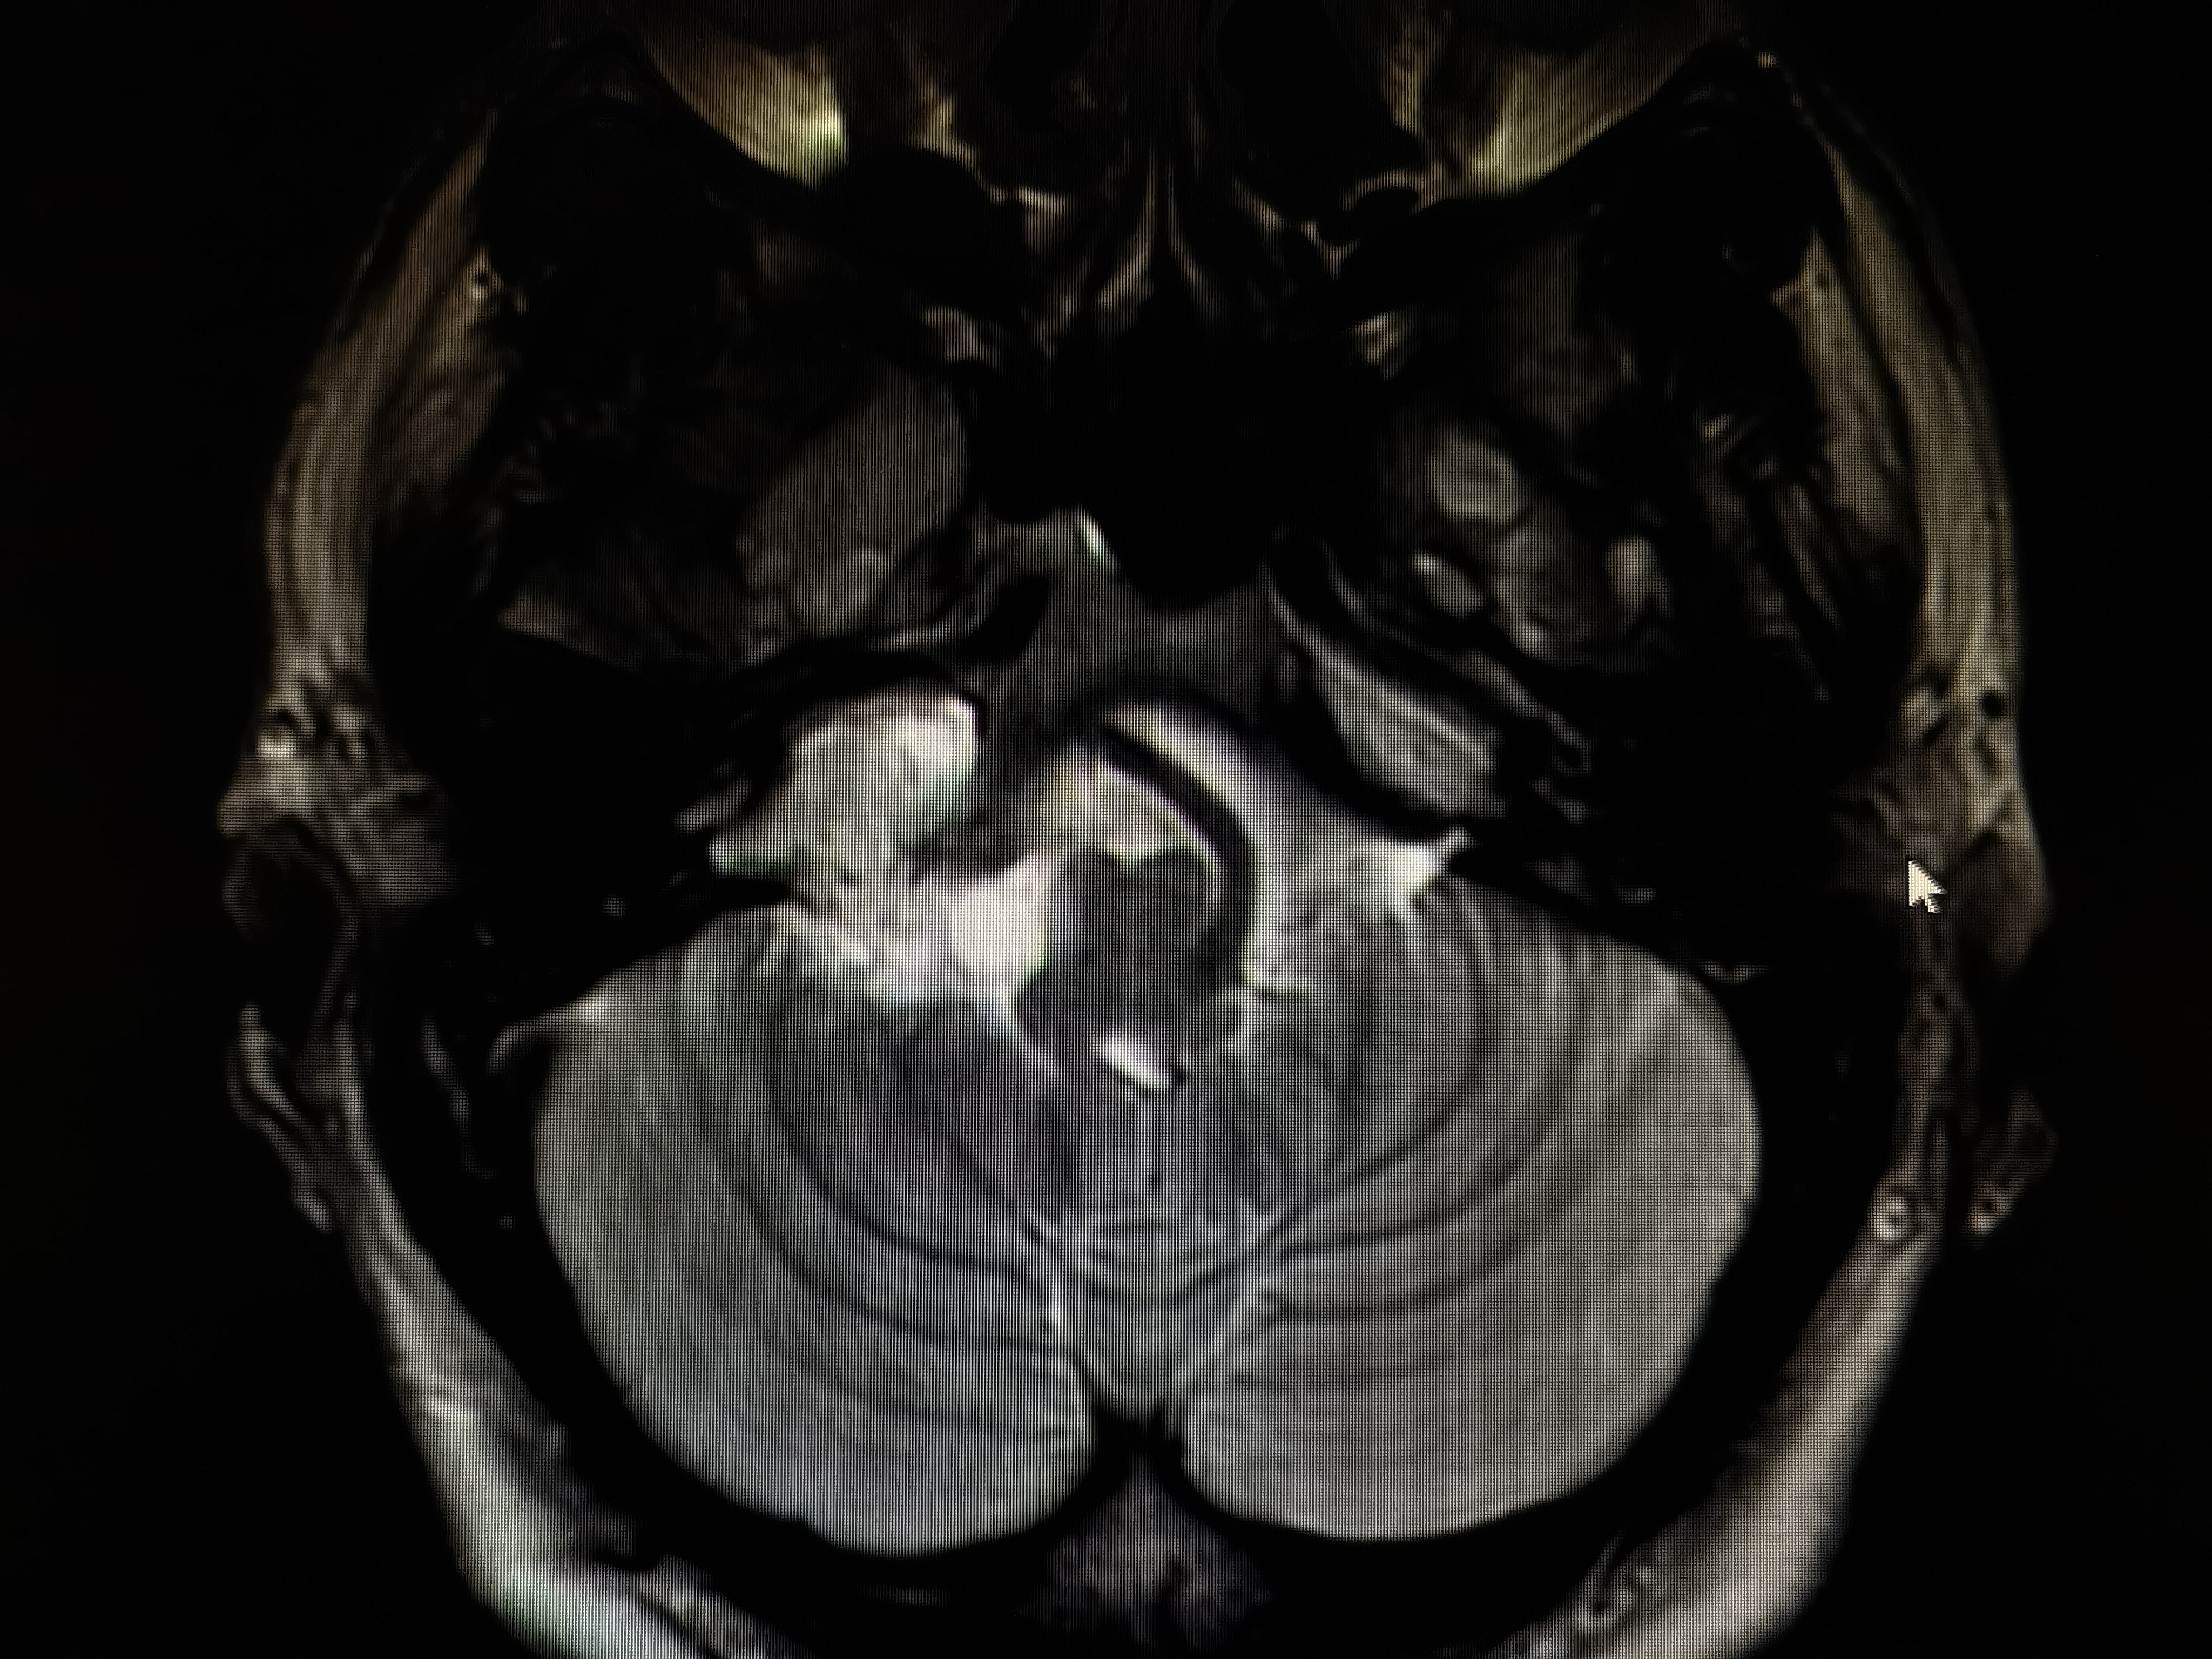

术前磁共振